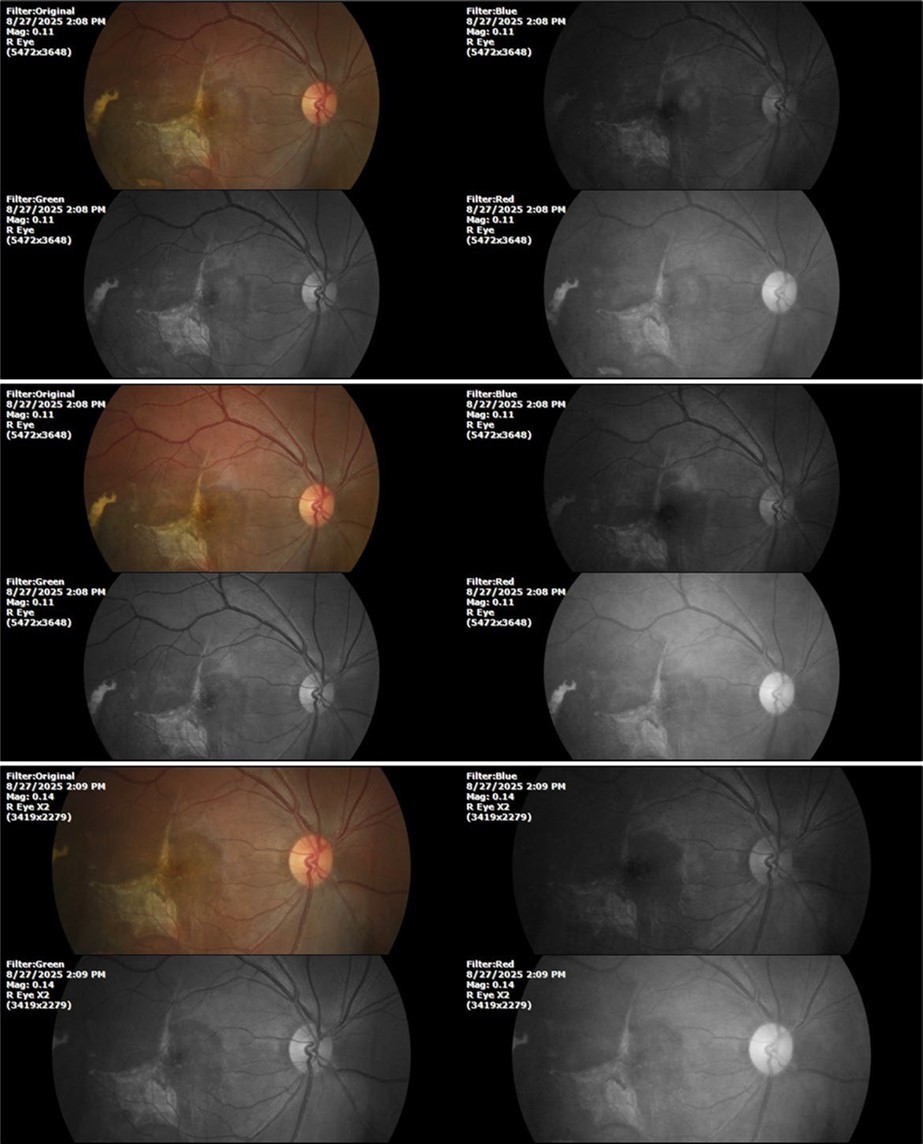

Figure 27.The three previous photographs of the right fundus show that the whitish mass composed mainly of phantom cells continues to decrease.

It's been fine, there's only a little veil that prevents it from seeing well completely, although it's very transparent (Figure 31, Figure 32, Figure 33, Figure 34, Figure 35, Figure 36).

94 %

62 x ́

++/++

Figure 31.The photograph of the right eye shows an almost normal mirror reflection, as well as a better pupillary dilation.

Figure 32.The macro photograph of the right eye shows us a cornea, anterior camera, and crystalline lens in very good condition.

Figure 33.The 3 previous photographs show that whitish mass has almost completely disappeared, and to date only a remnant remains on the left side of the photograph. The chorioretinal scar that is now observed corresponds to the area affected by the blunt trauma, which presumably caused rupture of Bruch's membrane. Fortunately, the macular region has recovered almost in its entirety, so the impairment in central vision was minimal.

Figure 8.The photograph of the superior temporal region of the retina of the right eye shows the extent of subretinal bleeding as well as retinal edema.

Figure 9.The extent of bleeding, mainly subretinal, is extensive and of significant volume, suggesting choroid rupture in this area.

Figure 10.The location of the bleeding is mainly subretinal, although blood is seen in minimal quantity in the vitreous body.